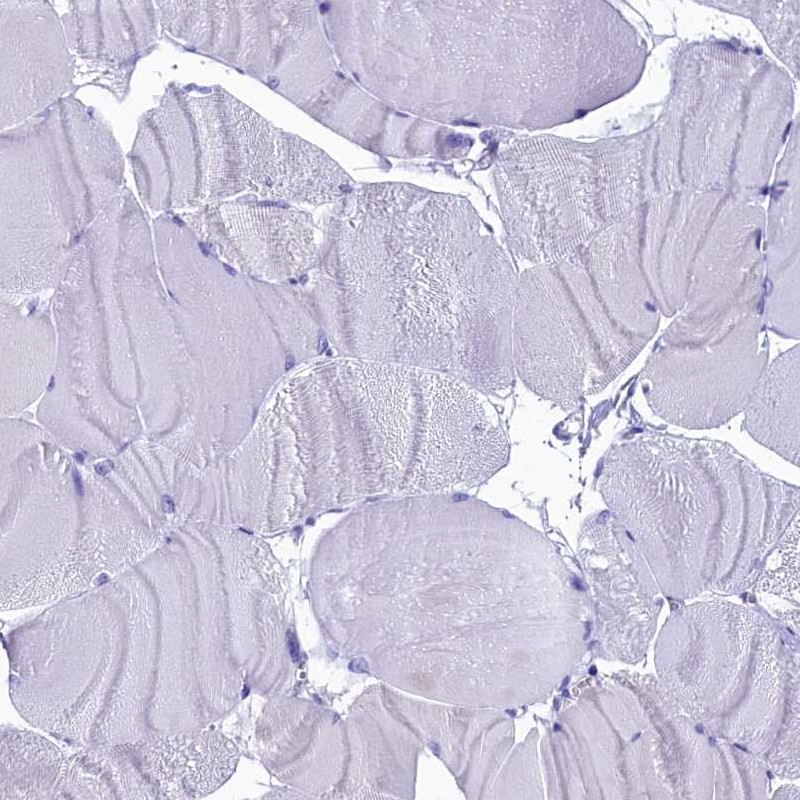

Immunohistochemistry analysis in human testis and skeletal muscle tissues using Anti-CIAPIN1 antibody. Corresponding CIAPIN1 RNA-seq data are presented for the same tissues.